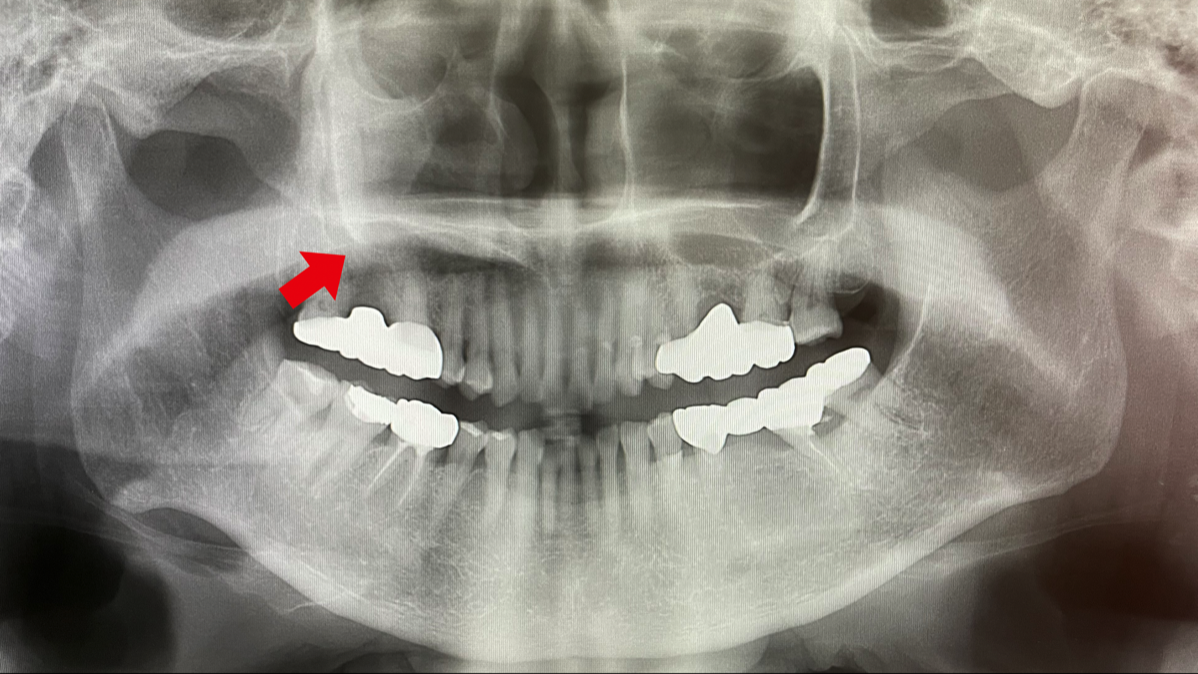

上あごの奥歯のむし歯に継発して歯根が感染を起こすと、鼻汁や鼻漏さえ伴う歯性上顎洞炎を生じることがあります。これも鼻が悪いからと放置して慢性化している人が多いように感じます。従来の歯科用エックス線撮影で左右の上顎洞の影の違いから見つかることもありますが、歯科用CT撮影ではより明確に上顎洞の状況を観察することができます。歯科での治療が中心になりますが、耳鼻科医との連携が必要になることもあります。

従来のX線撮影では、赤い矢印側で歯の上方が反対側に比べてやや白く見えるが明瞭ではない。